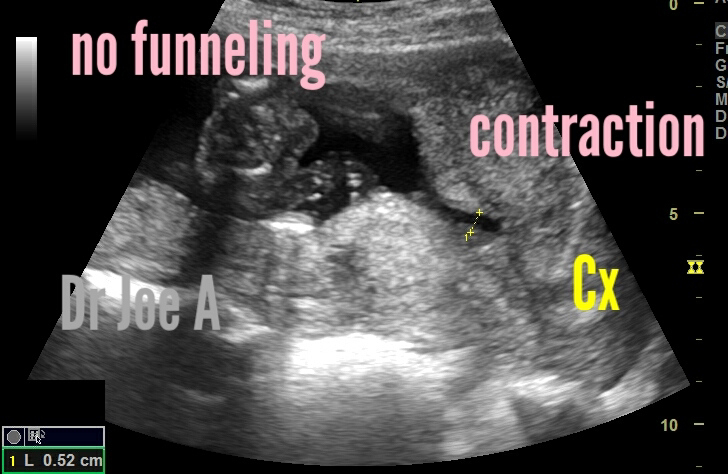

Contraction of lower uterine segment and not funneling

A 2nd trimester pregnancy underwent sonography for discharge PV.

Ultrasound imaging was done and showed these findings:

Before contraction of lower segment of uterus, there is no suggestion of funneling.

Over a period of 10 minutes there's apparently "funneling" in this region.

However the cervical length is at 3.7 cms and apparently normal.

Note also: the thickening of lower segment uterine myometrium due to contraction.

All these point to: contraction of lower segment of uterus and rule out funneling of cervix.

So how to distinguish between true funneling from lower uterine segment contraction:

Distinguishing between a contraction of the uterus and funneling of the cervix on ultrasound imaging can be challenging. However, there are certain characteristics that can help differentiate between the two in a 2nd trimester pregnancy.

1. Contraction of the uterus:

A contraction of the uterus is typically associated with temporary tightening and relaxation of the uterine muscle. It can cause a transient change in the shape of the uterus, but it doesn't involve the cervix itself. When evaluating an ultrasound image, look for the following signs:

- Irregular shape: Contractions may cause the uterus to appear irregularly shaped with areas of increased and decreased thickness.

- Transient changes: The alterations in the uterine shape due to contractions are often temporary, and the uterus should return to its normal appearance after the contraction subsides.

- Absence of funneling: Funneling of the cervix is not typically associated with contractions of the uterus. The cervix should remain closed and maintain its normal shape.

2. Funneling of the cervix:

Cervical funneling refers to the opening and shortening of the cervical canal, which may indicate a potential risk for preterm labor. When assessing an ultrasound image, consider the following characteristics:

- Beak-like appearance: Funneling of the cervix can present as a dilated and shortened cervical canal with a beak-like appearance. It may appear as a "funnel" or "v" shape in the ultrasound image.

- Structural changes: Unlike contractions, funneling of the cervix is more likely to persist and can be observed consistently throughout the ultrasound examination.

- Cervical length measurement: Cervical length is an essential parameter evaluated during ultrasound scans. Funneling is often associated with a shorter cervical length, which indicates an increased risk of preterm labor.